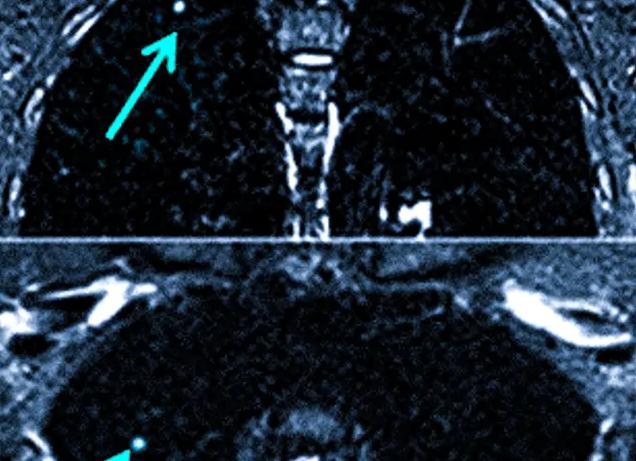

МРТ локтевого сустава дает возможность получить точный результат исследования таких структур дистальной части плеча и проксимальной части предплечья: